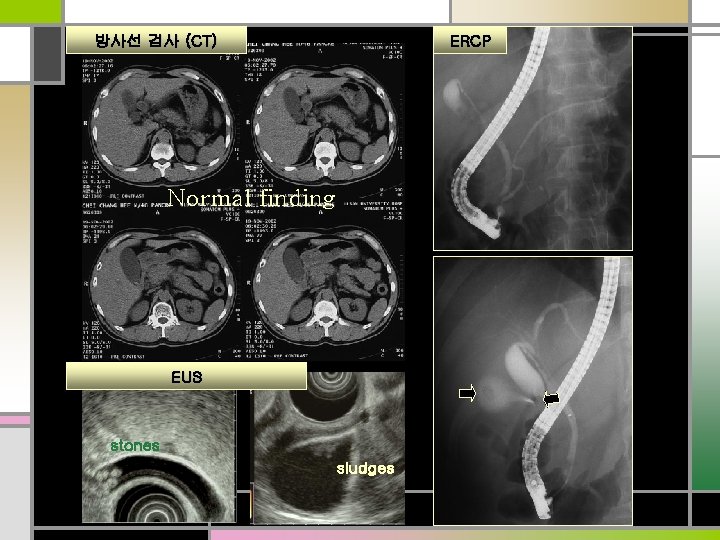

ERCP 방사선 검사 (CT) Normal finding EUS stones sludges

Diagnosis Acute (biliary) pancreatitis GB stones Treatment ERCP 꼭 해야 하나? ERCP with EST (Endoscopic sphincterotomy) Cholecystectomy C-duct P-duct